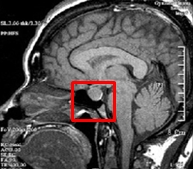

이것이 고정 틀을 사용해 얻은 MRI사진입니다. 주변 뇌 조직과 엄밀하게 구분해서 뇌하수체 종양의 위치를 파악하고 있습니다. 또 주변에 시신경이 가까이 있습니다. 시신경에 손상을 주면 안 되죠. 시신경과 종양의 위치를 정확하게 파악해서 컴퓨터로 치료 계획을 수립합니다.